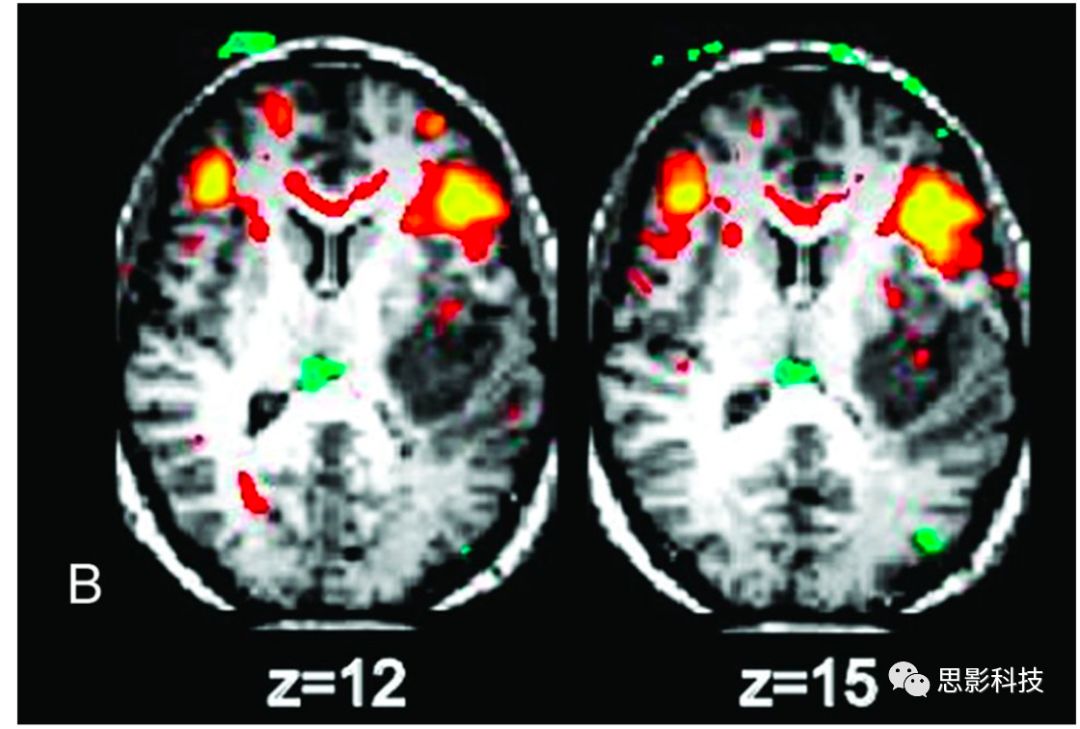

3的結果顯示出WMBOLD效果的主流視圖示例。作者通過顯示與左側Broca區(qū)域高度相關的體素,從而顯示了在靜息態(tài)下與語言表達相關的腦區(qū)。其中,如預期一致,右側額下回是該環(huán)路的一部分。但是該文章中未解釋清楚的是,與種子點高度相關腦區(qū)還包括位于胼胝體中呈新月形分布的體素區(qū)域(這是白質區(qū)域的)。靜息態(tài)下的白質功能連通性容易被忽視,因為這樣的發(fā)現(xiàn)通常是不會被考慮的,而相比而言,皮層才是主要會被納入討論的區(qū)域。通過對大量其他的研究進行仔細檢查,發(fā)現(xiàn)結果中存在通過閾值后的WM陽性結果,而這些體素都是被原作者所忽略的(這種情況是一直出現(xiàn)在相關文獻中的,基本上大家都不對白質區(qū)域出現(xiàn)的結果進行解釋,甚至是不愿意看到白質部分出現(xiàn)結果的,常規(guī)的操作是使用基于灰質概率的mask來“過濾”白質上可能存在的結果,現(xiàn)在看來,我們可能忽略了一些重要的信息)。

Fig 3. 靜息態(tài)MRI中,基于左側Broca區(qū)域作為種子點識別出與語言相關腦區(qū)。